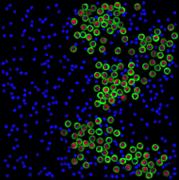

appropriate simulation algorithm. Figure 2 shows some examples of the obtained

Figure 2. Simulated synthetic images

images.similarity of experimental and generated synthetic images is not enough

real experimental images. That is why numerical comparison of the available

experimental images of cancer tumors and reproduced synthetic images was drawn.

The analysis of the intensity histograms of the affected

cells nuclei on simulated and experimental images in three colour channels was

conducted. The results showed similarity of the images intensity. The χ2 goodness of fit was used

to verify the quality of modelling and showed that the values did not exceed

critical values of χ2 at a significance level of 0.95

indicating that the statistical conditions of χ2 were satisfied., the

equivalent radii of nuclei on the experimental image were compared with those

on the simulated synthetic image. The χ2 goodness of fit was used

again for the objects distribution histogram according to the value of their

equivalent radii to check their conformity with the laws of distribution. The

calculation of χ2 values for 19 degrees of freedom

gave 9.61 which was less than the critical value of χ2 equal to 10.1 at a

significance level of 0.95.the process of cancer tumor cells modelling several